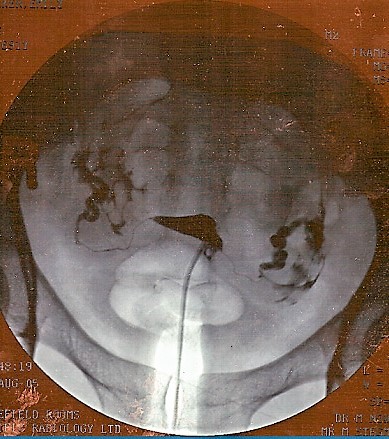

In the image below, the small black triangle shape in the middle is a normal womb filled with dye. The dye comes in through the tube which is at the base of the triangle and goes out to the edge of the photo. There are two very thin lines of dye coming away from the points of the triangle and these are normal Fallopian tubes, filled with dye. The larger areas of dye at either side is where the dye has spilled out of the normal tubes.

Hysterosalpingogram

© By jemsweb [CC BY-SA 2.0 (https://creativecommons.org/licenses/by-sa/2.0)], via Wikimedia Commons